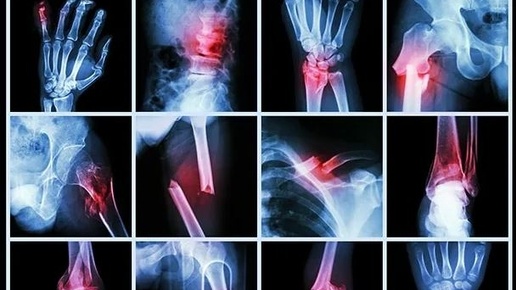

ЧТО ДЕЛАТЬ В ПЕРВЫЕ ЧАСЫ И ДНИ ПОСЛЕ ТРАВМЫ? Краткое руководство к действию, чтобы себе не навредить. Каждый из нас когда-нибудь получал травму: подворачивал ногу, падал, ударялся обо что-то во время бытовой активности или занятий спортом. Боль во время движения или в покое, отек, местное повышение температуры и гематома - симптомы, которые сигнализируют о возможном повреждении костей, связок или суставов. Первые 3-10 дней после травмы являются острым периодом, во время которого ткани активно заживают, и основная задача в это время - не мешать этому процессу! Что делать, чтобы себе не навредить? ❗Обратитесь к травматологу...